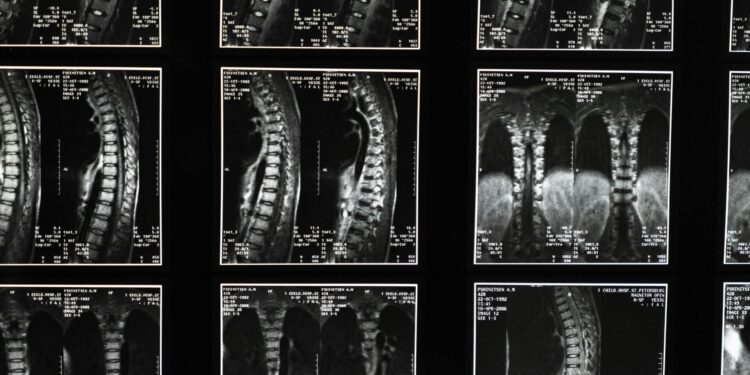

Israel se prepara para realizar o primeiro implante de medula espinhal humana do mundo usando células do próprio paciente — um avanço médico que poderá permitir que pacientes paralisados voltem a ficar de pé e andar, anunciou a Universidade de Tel Aviv na última quarta-feira (20).

A cirurgia está prevista para os próximos meses e representa um marco histórico na medicina regenerativa.

Segundo dados da Organização Mundial da Saúde (OMS), mais de 15 milhões de pessoas no mundo todo vivem com lesões na medula espinhal, sendo a maioria resultante de causas traumáticas, como quedas, acidentes de trânsito e violência.

Mesmo com os avanços da medicina, atualmente, lesões na medula espinhal não podem ser totalmente curadas, e, portanto, o tratamento se concentra na estabilização do paciente, na prevenção de danos adicionais e na maximização da função.

O atendimento de emergência geralmente envolve a imobilização da coluna, a redução da inflamação e, por vezes, a realização de cirurgia para reparar fraturas ou aliviar demais pressões.

Um dos líderes do projeto que pode inovar a medicina,  o professor Tal Dvir, chefe do Centro Sagol de Biotecnologia Regenerativa e do Centro de Nanotecnologia da Universidade de Tel Aviv, explica que é a “medula espinhal transmite sinais elétricos do cérebro para todas as partes do corpo”.

Quando ela é rompida por um trauma — como um acidente de carro, uma queda ou um ferimento em combate — a corrente se rompe. Imagine um cabo elétrico cortado: quando as duas extremidades não se tocam mais, o sinal não consegue passar e o paciente permanece paralisado abaixo da lesão”, disse ao Jerusalem Post.

Diferentemente de outros tecidos, os neurônios da medula espinhal não conseguem se regenerar de maneira natural e, com o tempo, o tecido cicatricial bloqueia os sinais restantes.

O procedimento da Universidade de Tel Aviv visa substituir a parte danificada por uma medula espinhal cultivada em laboratório que se funde com o tecido saudável acima e abaixo da lesão.